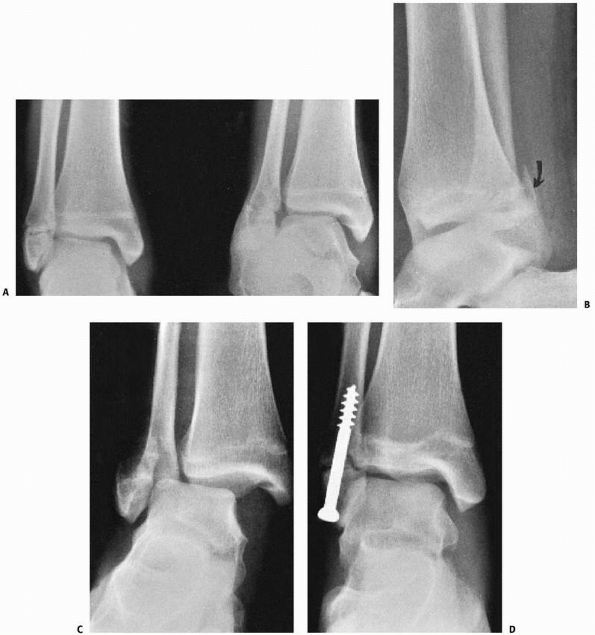

|

FIGURE 26-22 Three-dimensional CT reconstruction of juvenile Tillaux fracture. A. Coronal CT image of minimally displaced juvenile Tillaux fracture. B. Sagittal CT Image of minimally displaced juvenile Tillaux fracture. C,D. Three-dimensional reconstruction of juvenile Tillaux fracture.

production of such images (Fig. 26-22). These images can assist with minimally

invasive approaches and the use of percutaneous reduction clamps and screws.